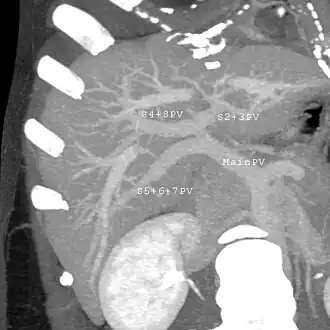

With the recent advances of noninvasive imaging, living liver donors usually have to undergo imaging examinations for liver anatomy to decide if the anatomy is feasible for donation. The evaluation is usually performed by multidetector row computed tomography (MDCT) and magnetic resonance imaging (MRI). MDCT is good in vascular anatomy and volumetry. MRI is used for biliary tree anatomy. Donors with very unusual vascular anatomy, which makes them unsuitable for donation, could be screened out to avoid unnecessary operations.

MDCT image. Portal venous anatomy contraindicated for liver donation